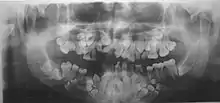

- Нарушения формирования корней, задержка в прорезывании молочных и постоянных зубов. Могут до 25-30-летнего возраста не меняться молочные зубы. Часто встречаются сверхкомплектные зубы.

Диагностика ключично-черепного дизостоза основана на клинических симптомах и рентгенологических исследованиях, которые включают изображения черепа, грудной клетки, таза и рук. Главный рентгенологический симптом — дефекты ключиц. Обычно отсутствует наружный (акромиальный) конец ключицы, в то время как внутренний (грудинный) конец присутствует. Но иногда ключица состоит из двух фрагментов. Полное отсутствие ключицы встречается редко.